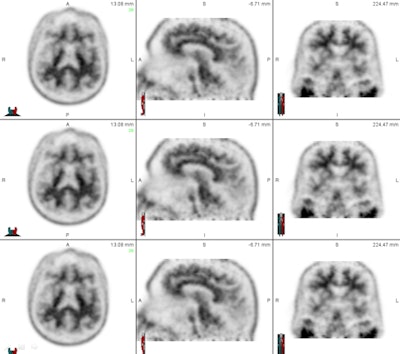

Dr. Ameya Nayate, a neuroradiology fellow in the department of radiology and nuclear medicine and lead author of the current study, noted that beta amyloid binds to brain regions such as the frontal lobe, temporal lobe, parietal lobe, and cingulate gyrus. These areas are associated with memory and other cognitive functions.

"With that specific information, we can look at those areas to determine if there is significant beta-amyloid deposition," Nayate said when he presented study results at the 2013 RSNA annual meeting. "However, in order to do that, we need to compare [those brain regions] to an internal standard: an area of the brain that does not have significant beta-amyloid deposition."

One such region is the cerebellum: Prior research has found no significant beta-amyloid deposition in this area, regardless of whether subjects are healthy or have Alzheimer's. SUV could potentially be measured in these regions and compared with SUV in the six brain regions susceptible to beta-amyloid deposits, producing an SUV ratio that indicates whether a patient has a higher burden of amyloid plaque. Physicians could use this information along with clinical findings to estimate a patient's risk of developing Alzheimer's disease.

The first 30 cases were used as a training exercise because not all five nuclear medicine readers were familiar with florbetapir PET imaging. Each of the 30 cases was read with SUVr information generated by image processing software (syngo Scenium, Siemens Healthcare) and then with no SUVr information.

The readers were asked to determine if there was significant beta-amyloid deposition based on their visual analysis (no SUVr data) and then with the additional SUVr information generated by Scenium. Cases were randomly assigned to four reading sessions, with 15 cases interpreted per session. No case was repeated within an individual session.